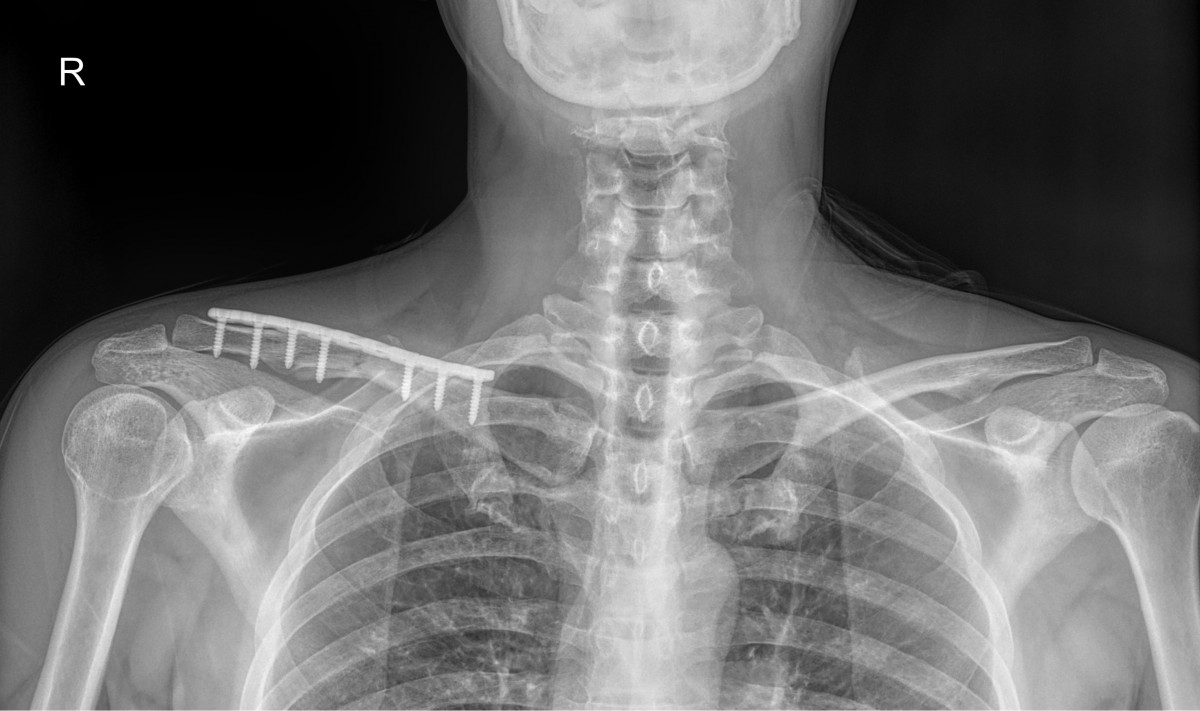

이재상원장님 어깨 골절 수술 곽평O 환자

dae765e4d9ac96aee867c9d6292d8784_1758002825_9963.jpg